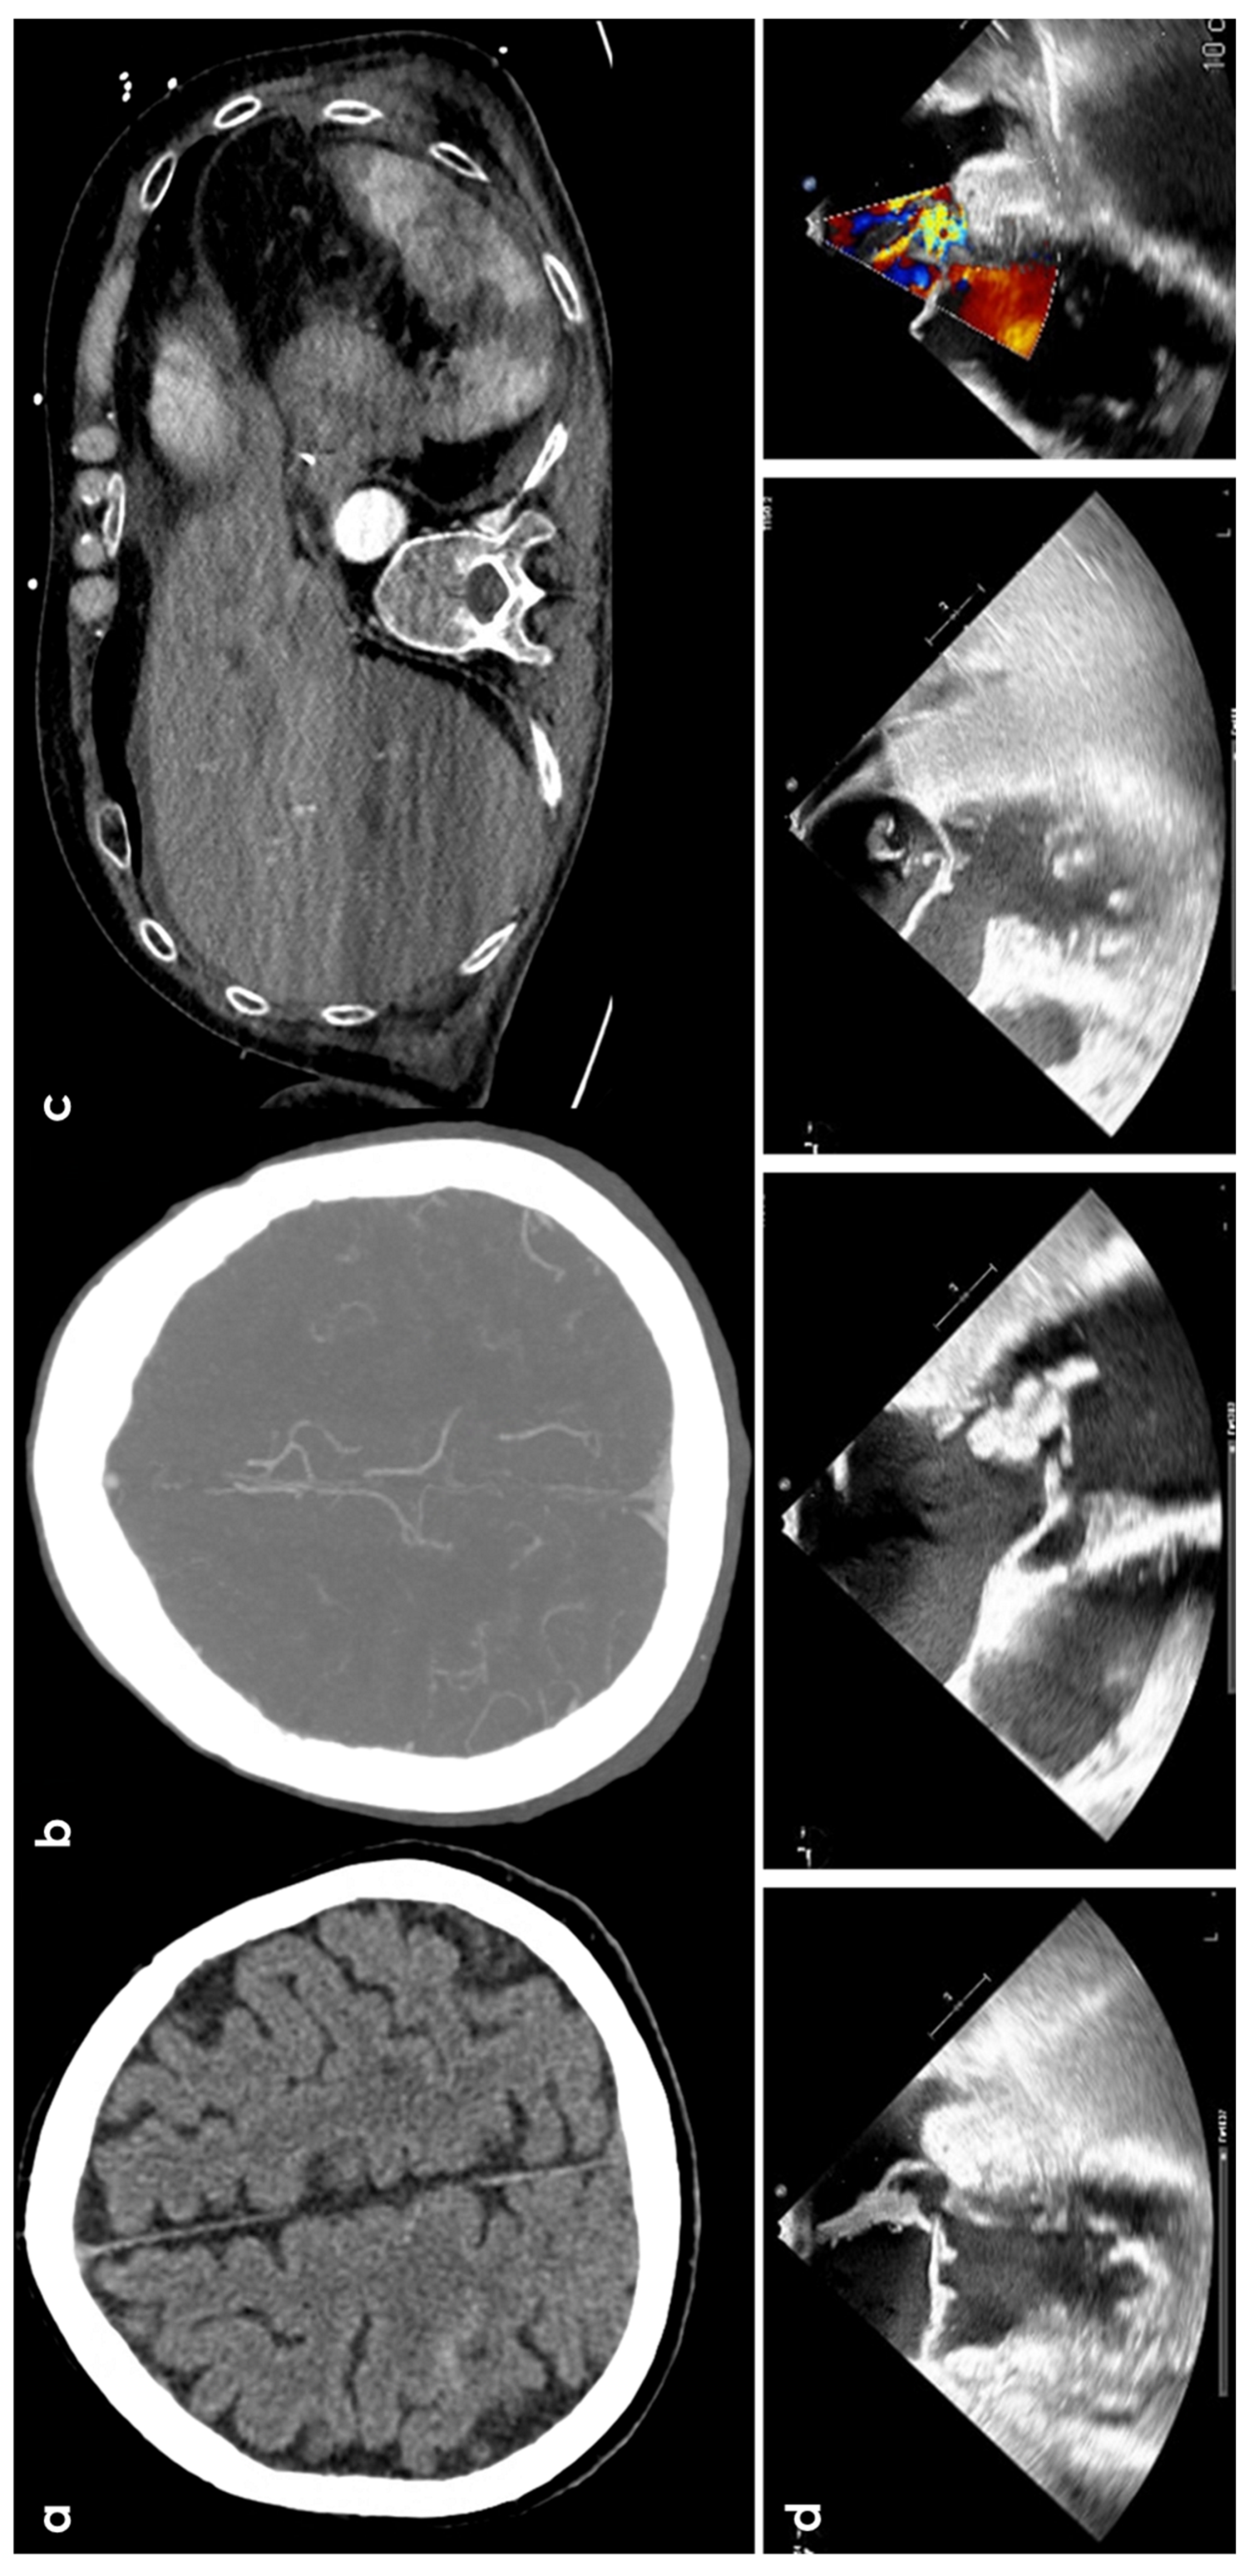

2. Epidemiology and Clinical Presentation

3.3. Infective Endocarditis

3.4. Cerebral Venous Thrombosis